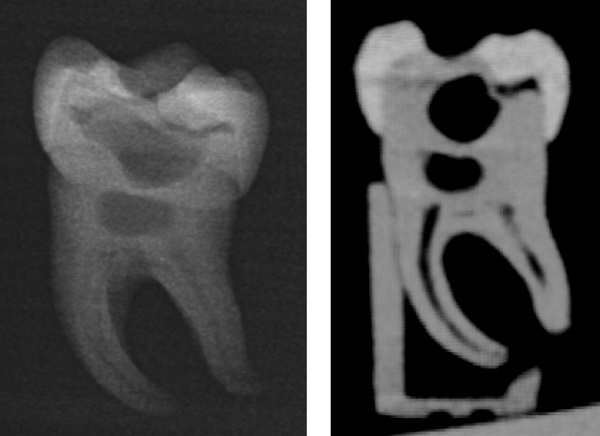

Bild 1: Rekonstruktion eines echten Zahnes basierend auf einer Mikro-CT-Aufnahme; v.l.n.r. Übersicht des ganzen Zahnes, Querschnitt des Zahnes; Wurzelkanäle und Pulpa. © Christian Höhne / UKW

Bild 3: Der gedruckte Zahn besitzt ein realistisches Röntgenverhalten. Links Aussehen des Zahnes bei einem Zahnfilm mit allen erkennbaren Innenstrukturen und rechts bei einer dreidimensionalen Röntgenaufnahme in Form eines so genannten DVT´s. © Christian Höhne / UKW